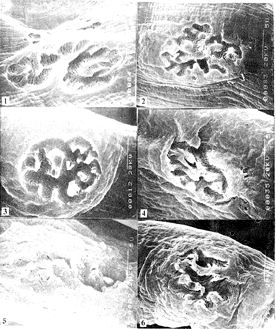

二、次级突触间隙观察 对照组眼肌次级突触间隙(图1)比口肌次级突触(图2)的数量多、长而大。但二者的形态相同,均呈裂隙状。

压榨面神经后第30天,10 s组眼肌次级突触间隙比口肌次级突触间隙数量少而浅;30 s组眼肌次级突触间隙(图3)比口肌次级突触间隙(图4)数量明显减少而且平滑。二者均比对照组的次级突触间隙的数量减少、变小、变浅。

压榨面神经后第60天、10 s组眼肌次级突触间隙(图5)比口肌次级突触间隙(图6)数量少。但二者均比第30天的次级突触间隙数量有所增加。30 s组二者与第30天的刺激突触间隙相比无明显改变,眼肌次级突触间隙比口肌次级突触间隙仍然数量减少而且平滑。

图1 对照组眼肌次级突触间隙

图2 对照组口肌次级突触间隙

图3 压榨面神经后第30天30 s组眼肌次级突触间隙

图4 压榨面神经后第30天30 s组口肌次级突触间隙

图5 压榨面神经后第60天10 s眼肌次级突触间隙

图6 压榨面神经后第60天10 s口肌次级突触间隙